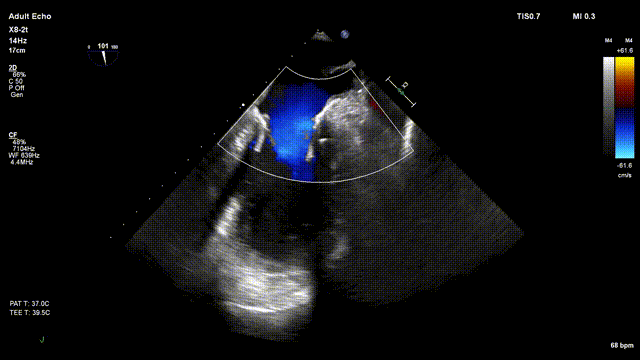

术中超声

手术在单纯超声引导下完成,采用左侧第六肋间微创切口心尖入路,在食道探头引导下,清晰识别MitraFix®输送系统准确跨瓣,超声科骆志玲主任、朱达主任通过Multivue在三维超声引导下精准定位瓣膜方位,在X-plane下精准定位瓣膜释放高度及保证系统的同轴性,最终将人工瓣膜准确释放于二尖瓣瓣环。

瓣膜释放后支架贴合牢固无瓣周漏,二尖瓣前向血流通畅, 左心室流出道通畅,流出到血流速度为0.4m/s。顺利撤出输送系统,由于患者心尖部位心肌壁只有4mm,潘湘斌院长亲自关闭心尖切口,顺利完成手术。